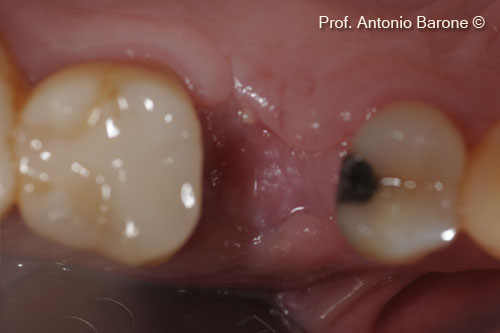

Một bệnh nhân nữ (54 tuổi) cho thấy răng bị gãy ở vị trí số 15.

Hình ảnh lâm sàng mặt nhai của một chiếc răng bị gẫy

Hình ảnh lâm sàng từ phía má của một chiếc răng bị gẫy